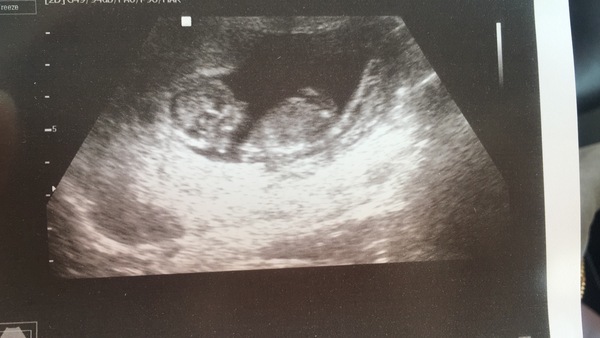

Anyone ever had any success predicting gender with the nub theory? I don't really get it. This is my 12week scan with my second baby. My sons scan was done at 10weeks so no visible nub to test the theory against!

I wouldn't read much into it. At my 12 weeks scan there was just 1 line and so everyone told me it was a boy. At my 20 week scan I was told he was in fact a she and there were 3 lines visible by that point.